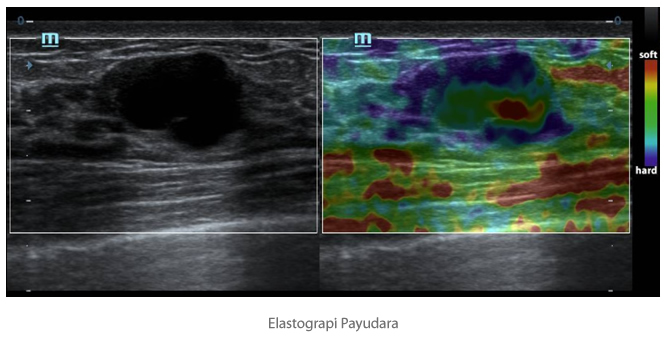

Natural Touch Elastography

Berdasarkan teknologi paten terbaru Mindray, Natural Touch Elastografi mengurangi ketergantungan pada teknik pengoperasian operator, sehingga meningkatkan produktivitas operator untuk kegunaan klinis yang lebih tinggi..

- Sensitivitas kepadatan lebih tinggi.

- Stabilitas dan keterulangan yang baik.